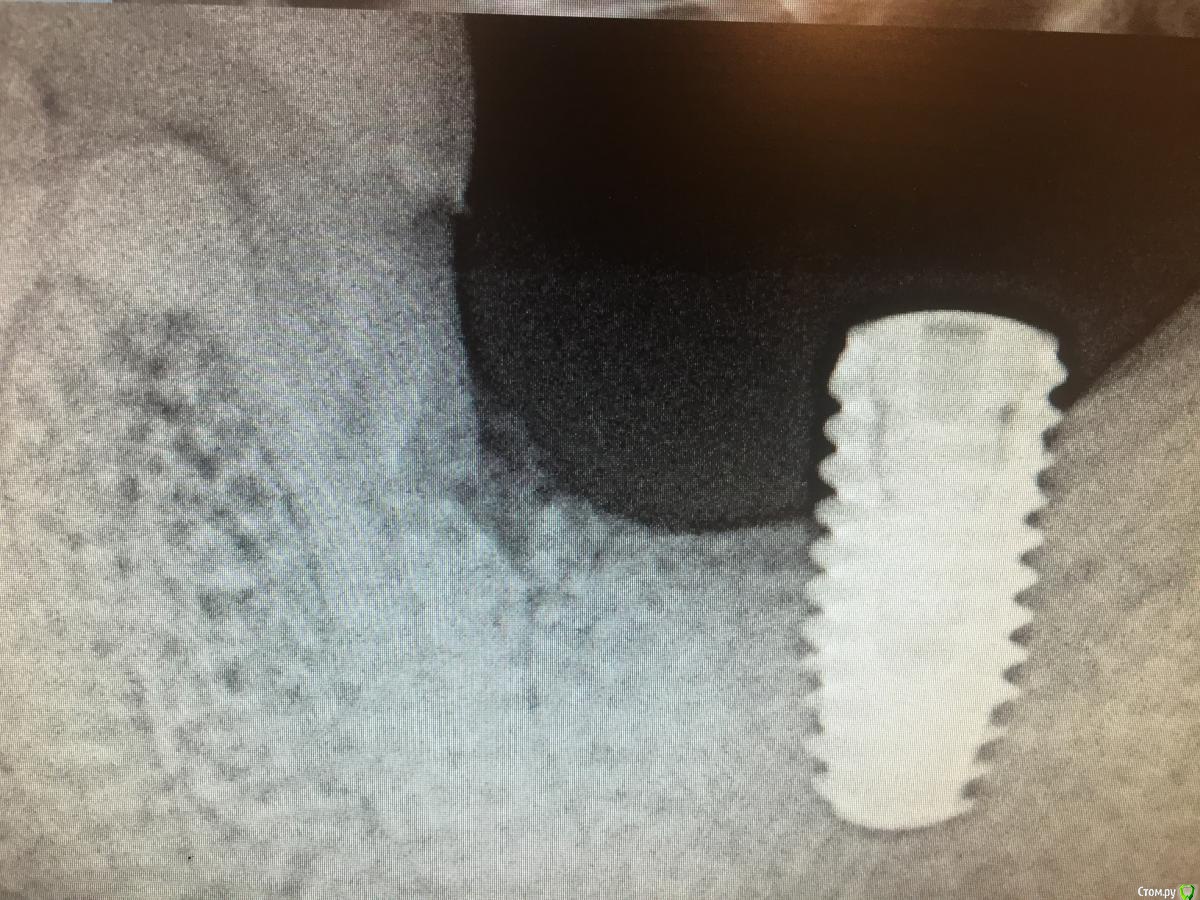

АнтонТЛТ Опубликовано 31 мая, 2020 Поделиться Опубликовано 31 мая, 2020 Был не давно фейл. Шестерка с пропилом дистального корня. Решили рискнуть и поставили 7ку. Всё было ок. Но потом кость ушла до уровня пропила и имплантат начал оголяться. В итоге шестерка и имплантат удалены. Буду ставить 2 имплантата. Если будет в той клинике смена на следующей неделе, то скину снимки. 2 Ссылка на комментарий

АнтонТЛТ Опубликовано 16 июня, 2020 Поделиться Опубликовано 16 июня, 2020 Был не давно фейл. Шестерка с пропилом дистального корня. Решили рискнуть и поставили 7ку. Всё было ок. Но потом кость ушла до уровня пропила и имплантат начал оголяться. В итоге шестерка и имплантат удалены. Буду ставить 2 имплантата. Если будет в той клинике смена на следующей неделе, то скину снимки.Постоянно забывал сфоткать 1 Ссылка на комментарий